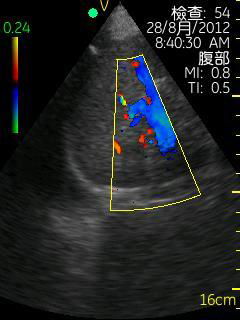

Vscan临床图片 腹部